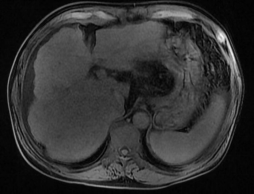

核磁检查,作为正常人肝脏,右为酒精性肝硬化(肝脏缩小,表面,凹凸不平,脾脏肿大)